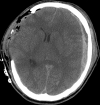

Traumatic intracranial pseudoaneurysms are a rare but severe complication following arterial injury. Pseudoaneurysm formation can occur secondary to blunt or penetrating trauma or iatrogenic injury. We report a case of traumatic pseudoaneurysm secondary to placement of an intracranial pressure (ICP) monitor. A 27-year-old man was involved in a motorcycle accident resulting in multiple intracranial hemorrhages. The patient underwent craniectomy and placement of an ICP monitor. 17 days later he developed dilation of his left pupil, with imaging demonstrating a new hemorrhage in the vicinity of the previous ICP monitor. A cerebral angiogram confirmed a left-sided distal M4 pseudoaneurysm which was treated by n-butyl cyanoacrylate embolization. Intracranial pseudoaneurysm formation following neurosurgical procedures is uncommon. Delayed intracranial hemorrhage in a region of prior intracranial manipulation, even following a procedure as 'routine' as placement of an ICP monitor, should raise the suspicion for this rare but potentially lethal complication.